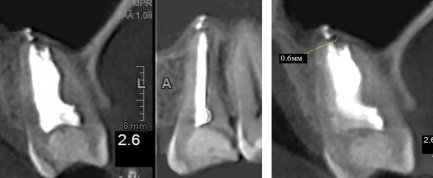

Начал разрушаться зуб, верхняя левая 6. Обратился к стоматологу. Сделали рентген, высверлили каналы, в общем, за несколько походов мне его нарастили.

Без нареканий ходил четыре года, недавно почувствовал боль при надавливании (и только в определенных направлениях).

Чувствуется, что внутри незначительное воспаление. Боль тупая, при надавливании - острая, простреливающая, при этом болит не всегда. Ближайшие две недели физически не смогу посетить стоматологию.

Не имея данных рентгенологического исследования, могу предположить хроническое воспаление на корнях (периодонтит), либо патологический зубодесневой карман.